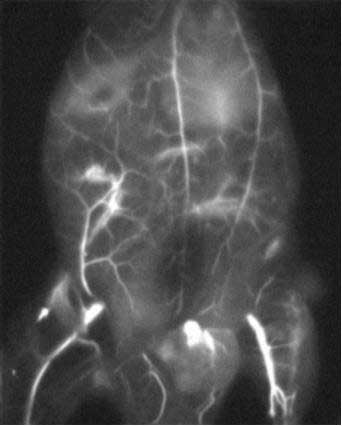

上轉(zhuǎn)換發(fā)光納米材料(UCNPs)具有熒光壽命長、潛在生物毒性低、穿透深度大、對生物組織損傷小且?guī)缀鯖]有背景光等顯著優(yōu)點(diǎn),近年來在生物成像及生物檢測等領(lǐng)域已經(jīng)得到廣泛應(yīng)用,下圖未上轉(zhuǎn)換納米顆粒在生物活體中進(jìn)行腫瘤標(biāo)記。

Figure 5.上轉(zhuǎn)換納米材料在腫瘤靶向成像中的應(yīng)用1